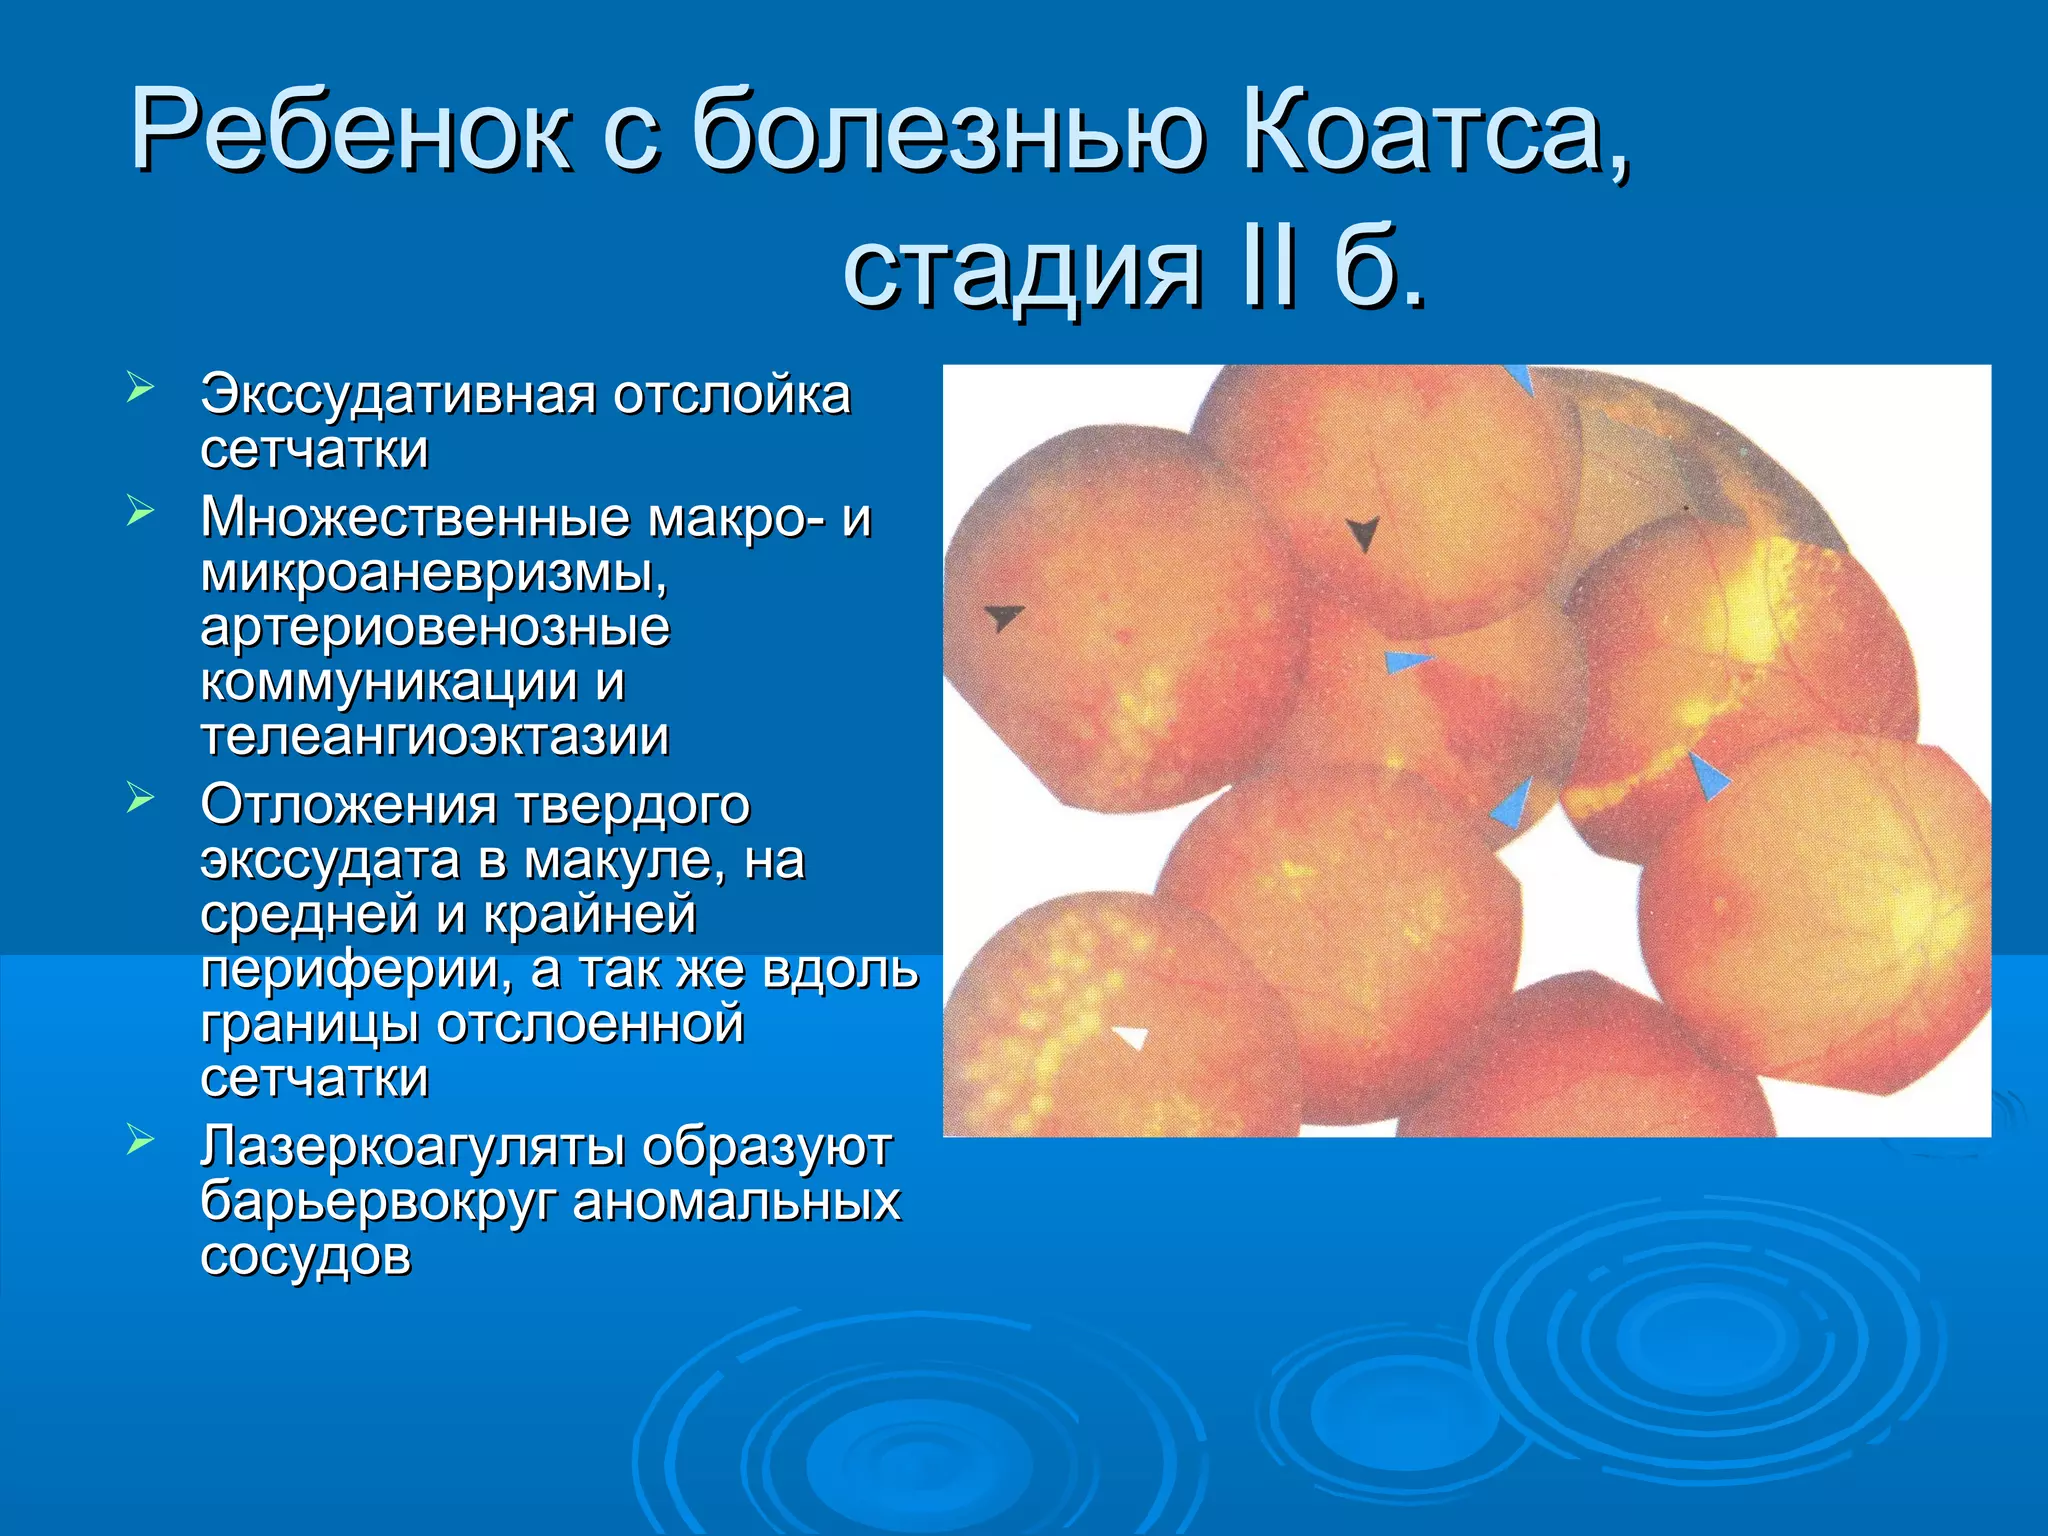

Болезнь Коатса - это идеопатическое заболевание, характеризующееся полиморфными изменениями сосудов сетчатки с массивной экссудацией, чаще всего у детей и подростков, с преобладанием среди мальчиков. Эпидемиология показывает, что заболевание проявляется, как правило, в возрасте 8-16 лет, но возможно его обнаружение и у взрослых. Основные проявления включают ретинальные аномалии, субретинальную экссудацию и постепенно прогрессирующую потерю зрения.